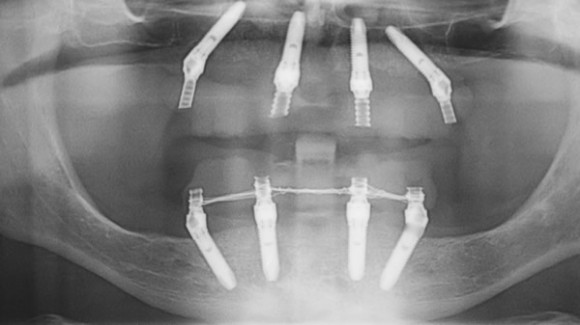

L’implantologia a carico immediato all on four utilizza impianti dentali inclinati tra i 30 ed i 45 gradi allo scopo di assicurare un solido appoggio alla protesi dentale.

Proprio per questo, l’implantologo, prima di attuare l’intervento prenderà in considerazione l’anamnesi del paziente e lo sottoporrà ad esami specifici tra cui una tac, una radiografia panoramica, un Ecg, esami del sangue e quant’altro.